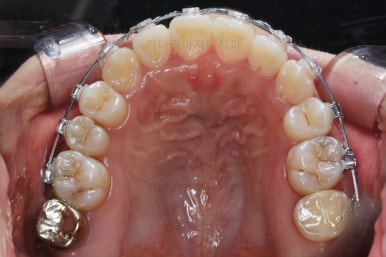

사용한 장치 : 자가결찰 세라믹(클리피씨) + 미니스크류

부분적으로 장치 셋팅을 다시 해줬고요.

밀고 당기기를 위해서 미니스크류를 셋팅했고요.

교합과 중앙선 및 디테일을 맞춰 나갑니다.